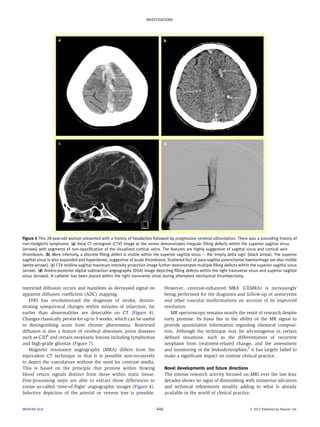

Figure 1 This 34-year-old woman had disseminated tuberculosis (TB) and multiple neurological signs and symptoms including headache, weakness and

lower cranial nerve palsies. (a and b) Coronal and axial post-contrast T1-weighted magnetic resonance (MR) images demonstrating obstructive hydro-cephalus,

multiple ring-enhancing tuberculomas (arrows) and prominent basal meningeal enhancement. (c) Sagittal post-contrast T1-weighted image of

the cervical spine demonstrates diffuse meningeal enhancement. Prominent enhancement involving the ventral surfaces of the pons and medulla

oblongata is particularly noteworthy (arrow). (d) Axial T2-weighted MR image through the thorax at the level of the upper mediastinum reveals multifocal

patchy pulmonary changes in keeping with active TB.